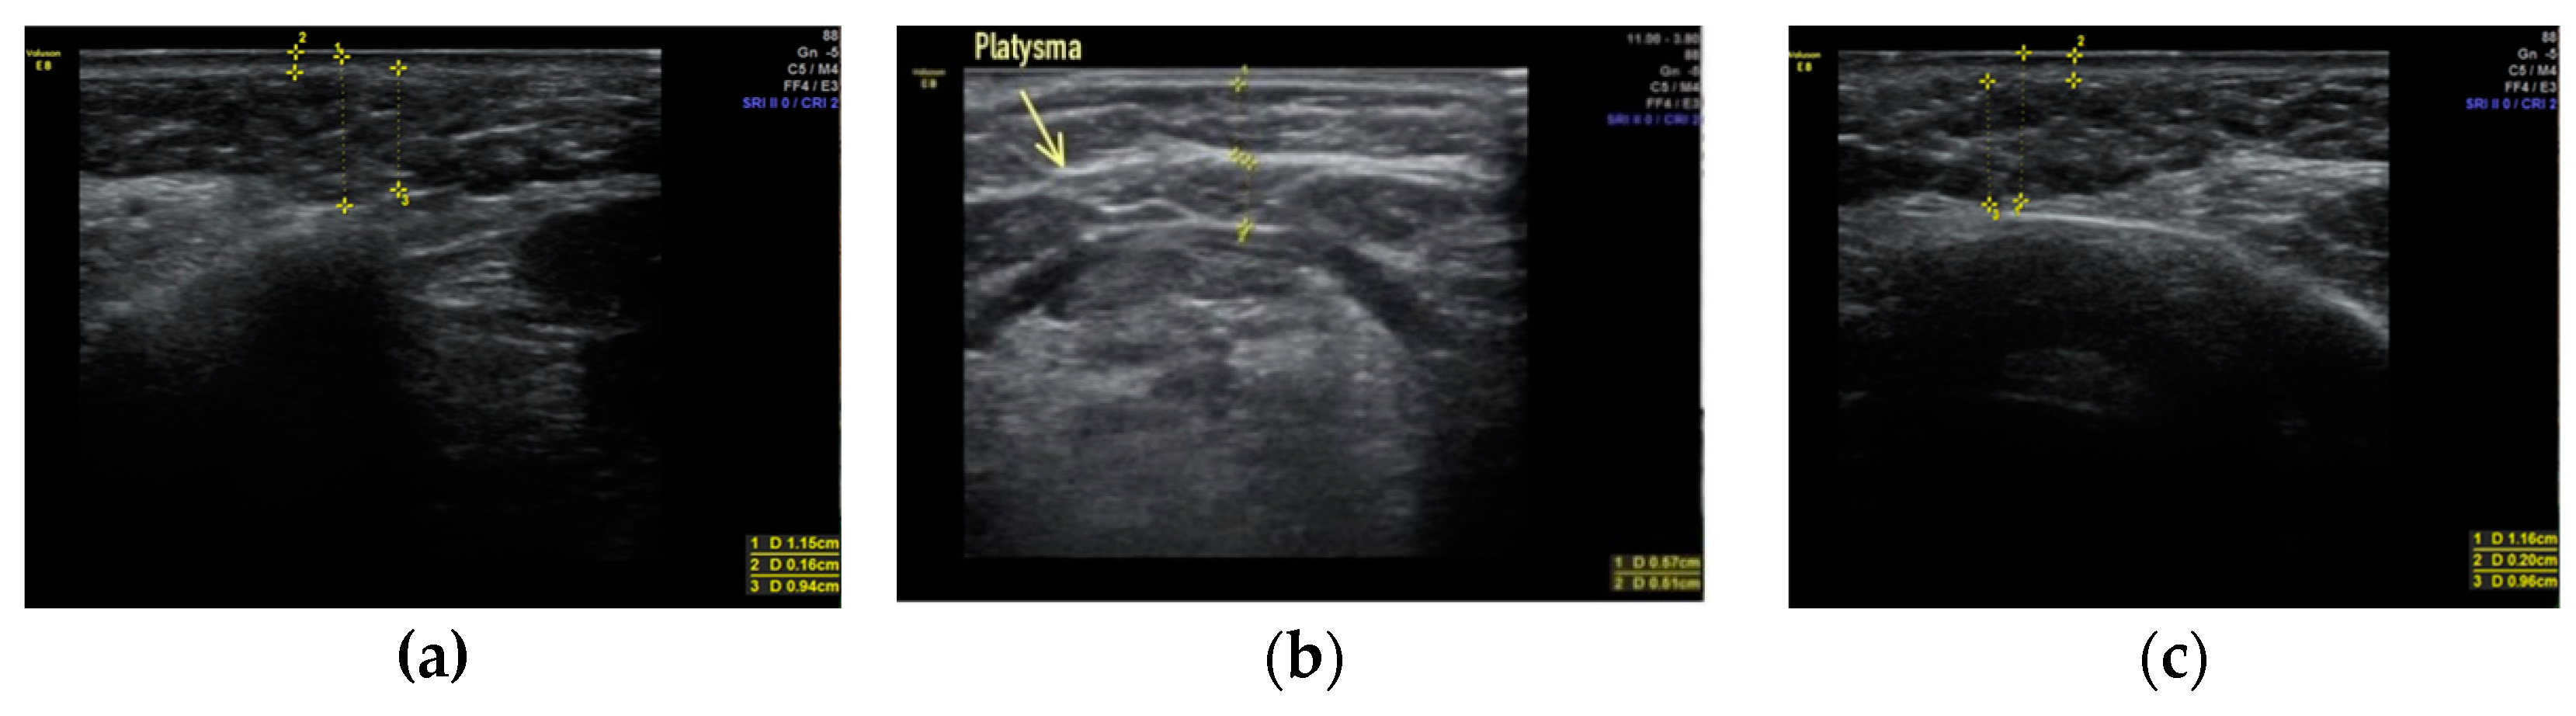

- Sharobaro, V.; Alimova, S.; Telnova, A.; Shamanaeva, L. Ultrasound diagnosis of age-related involutional changes in the lower third of face and neck to determine treatment techniques. Pak. J. Med. Sci. 2021, 37, 272–276. [Google Scholar] [CrossRef]

- Alimova, S.M.; Sharobaro, V.I.; Telnova, A.V.; Stepanyan, E.E. Planning of methods of surgical correction of soft tissues of the face and neck. Med. Vis. 2021, 25, 47–52. [Google Scholar] [CrossRef]